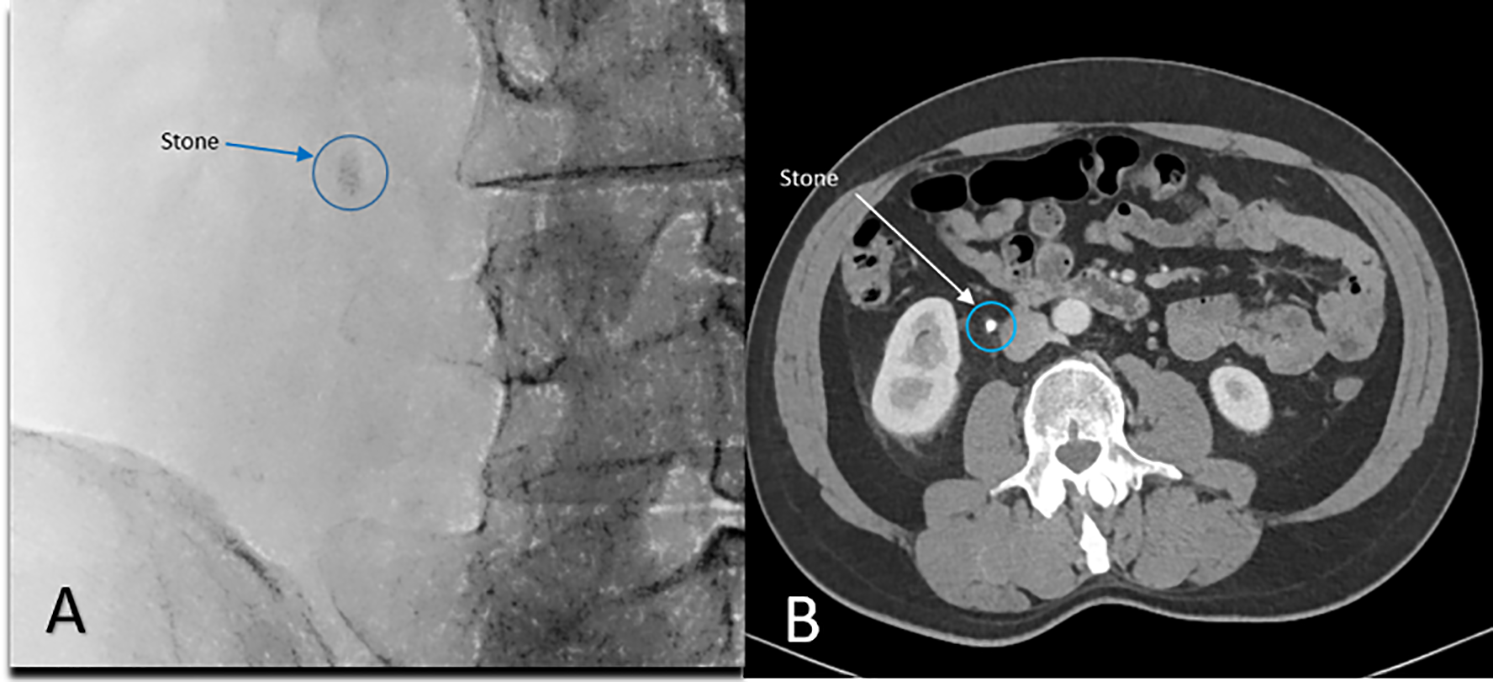

We have included a sample demonstrative case of a 7 mm right ureteral stone, as can be seen in Figure 2. The stone was not amenable to the standard retrograde stenting approach, since after passing a guidewire alongside the stone, the degree of ureteral occlusion prevented the safe passage of a double-J stent. A ureteral dilator was positioned close to the stone tip as described above and shown in Figure 3A,B, followed by passage of a double-J stent through the ureteral dilator sheath as seen in Figure 3C.

FIGURE 2. Mid-distal ureteral stone measuring 7 mm. (A) Intraoperative fluoroscopy; (B) Pre-operative CT scanning